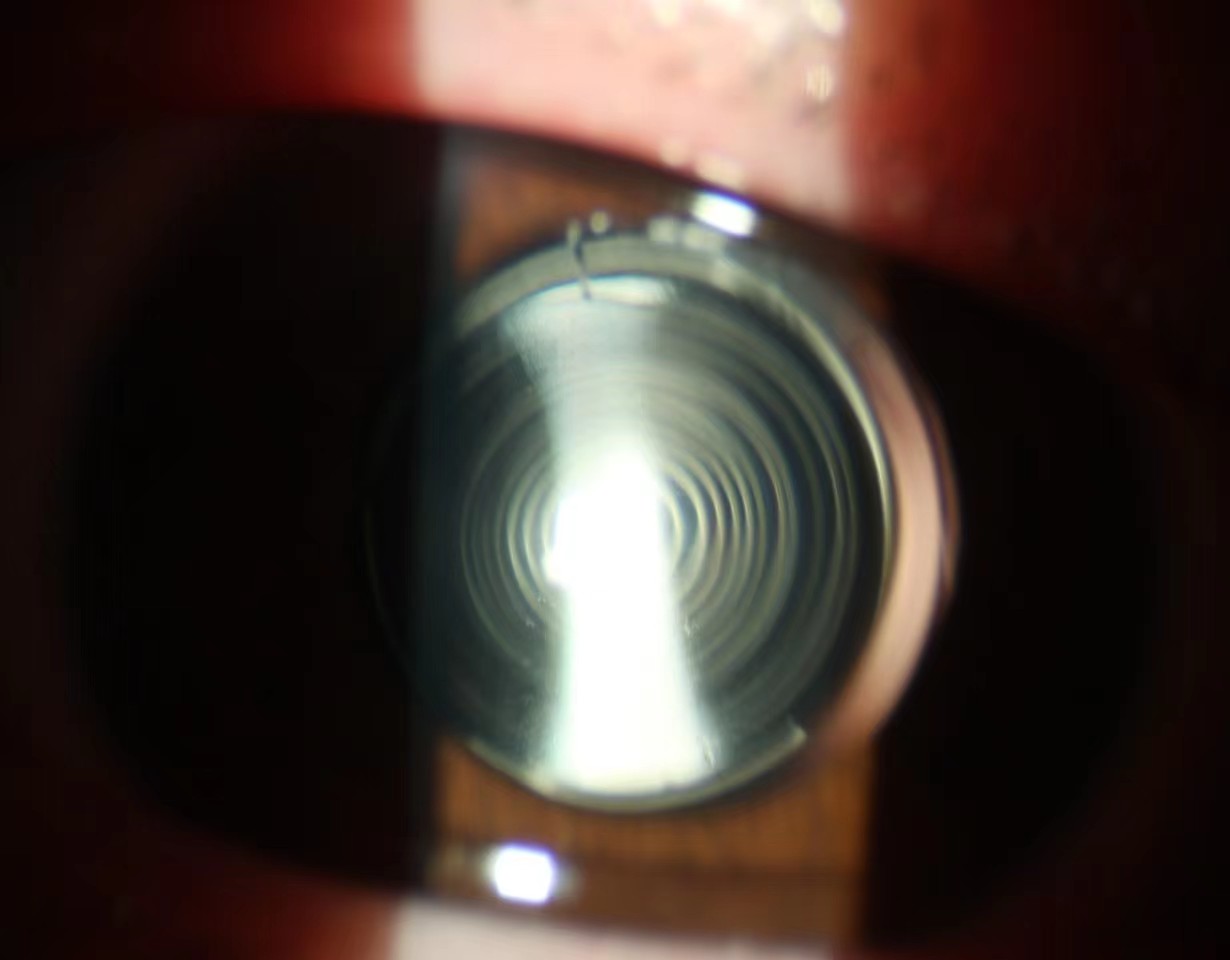

眼科就诊。由于患者需要术后尽快能够投入学习中,术前沟通中流露出对术后视力很高的期望,希望术后不但能够看远而且能够近距离连续阅读。此类患者常规的解决方案是使用多焦点人工晶体恢复术后远、中、近视力,但术前检查发现患者双眼均有350度以上的散光,不符合常规多焦点人工晶体植入的适应证。面对患者和家属殷盼的目光,经过讨论、重复测量和反复验算,为患者采取超声乳化白内障吸除联合双焦点散光型人工晶体植入手术,同时根据先天性白内障不确定因素备用了单焦点人工晶体植入术联合术后眼镜矫正的替补方案,最终在手术室和麻醉科配合下张坚主任主刀,仅用时15分钟即顺利完成手术。次日晨患者术眼残余散光不足25度,人工晶体光学中心与瞳孔中心重合,散光轴位与术前设计的100°角度分毫不差,恢复的远视力达1.0,中视力和近视力均为0.8,完美的达到术前预定恢复视力脱镜的效果。

目前白内障手术从复明手术发展到屈光性白内障手术,患者不但要求能看到,还要看得清和看得舒适。功能性人工晶体解决患者这些需求应运而生,主要包括散光型人工晶体和多焦点人工晶体,其中散光型人工晶体主要矫正患者术前较大散光以提高裸眼视力,手术前要进行眼表散光标志的标记,术中严格按术前计算标记的轴位将人工晶体置于指定轴线位置;而多焦点人工晶体则是为了改变单焦晶体不能远近视力兼得的缺点,要求患者自身光学条件良好,术中人工晶体中心定位良好。该患者自身光学特性不能满足常规多焦点人工晶体要求,需联合散光矫正才能获得满意作用,而散光型多焦点人工晶体设计制造同样复杂,目前仅有双焦点散光型人工晶体在临床应用,该类人工晶体度数计算牵涉因素多,术中操作复杂,不但要对齐瞳孔中心、光学中心,还要对齐散光轴线,对术前测量、设计计算及手术团队要求很高。